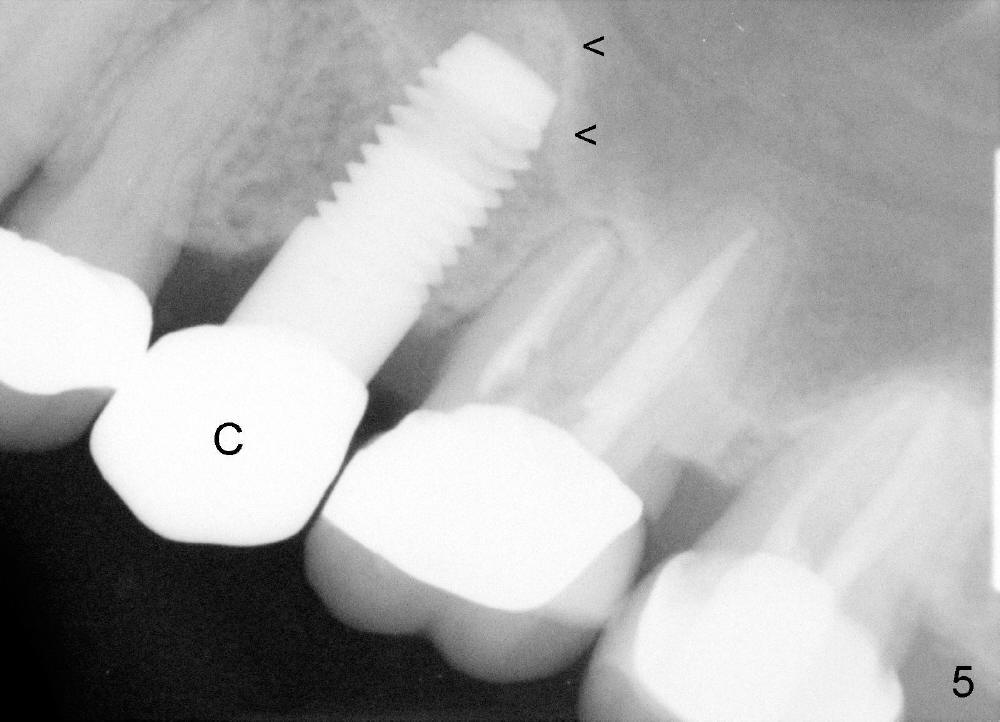

A 59-year-old lady used to have a 3-unit bridge in the upper left quadrant. A 4.5x6mm Bicon implant (Fig.1 B without extruding into the sinus) was placed in the atrophic pontic area 5 months earlier. When the abutment (A) was removed, the implant came out. The osteotomy was processed with a 4.5x14 mm tapered tap, which was unstable. When a 4.8 mm cylindrical tap was placed (past the sinus floor), it was tight (Fig.2). A 5x14 mm cylindrical implant (Fig.3 I) was inserted with elevation of the apparent sinus floor (>, no allograft used in case of sinus infection). Seven months postop, the density of sinus floor increases (Fig.4 <). The implant is stable and processed for crown (Fig.5 C, different view of the lifted sinus floor (<)). While sinus floor density is decreasing, the mesial and distal bone density is increasing 6 months (Fig.6), 1 year 6 months (Fig.7) and 3 year 6 months (Fig.8) post cementation.